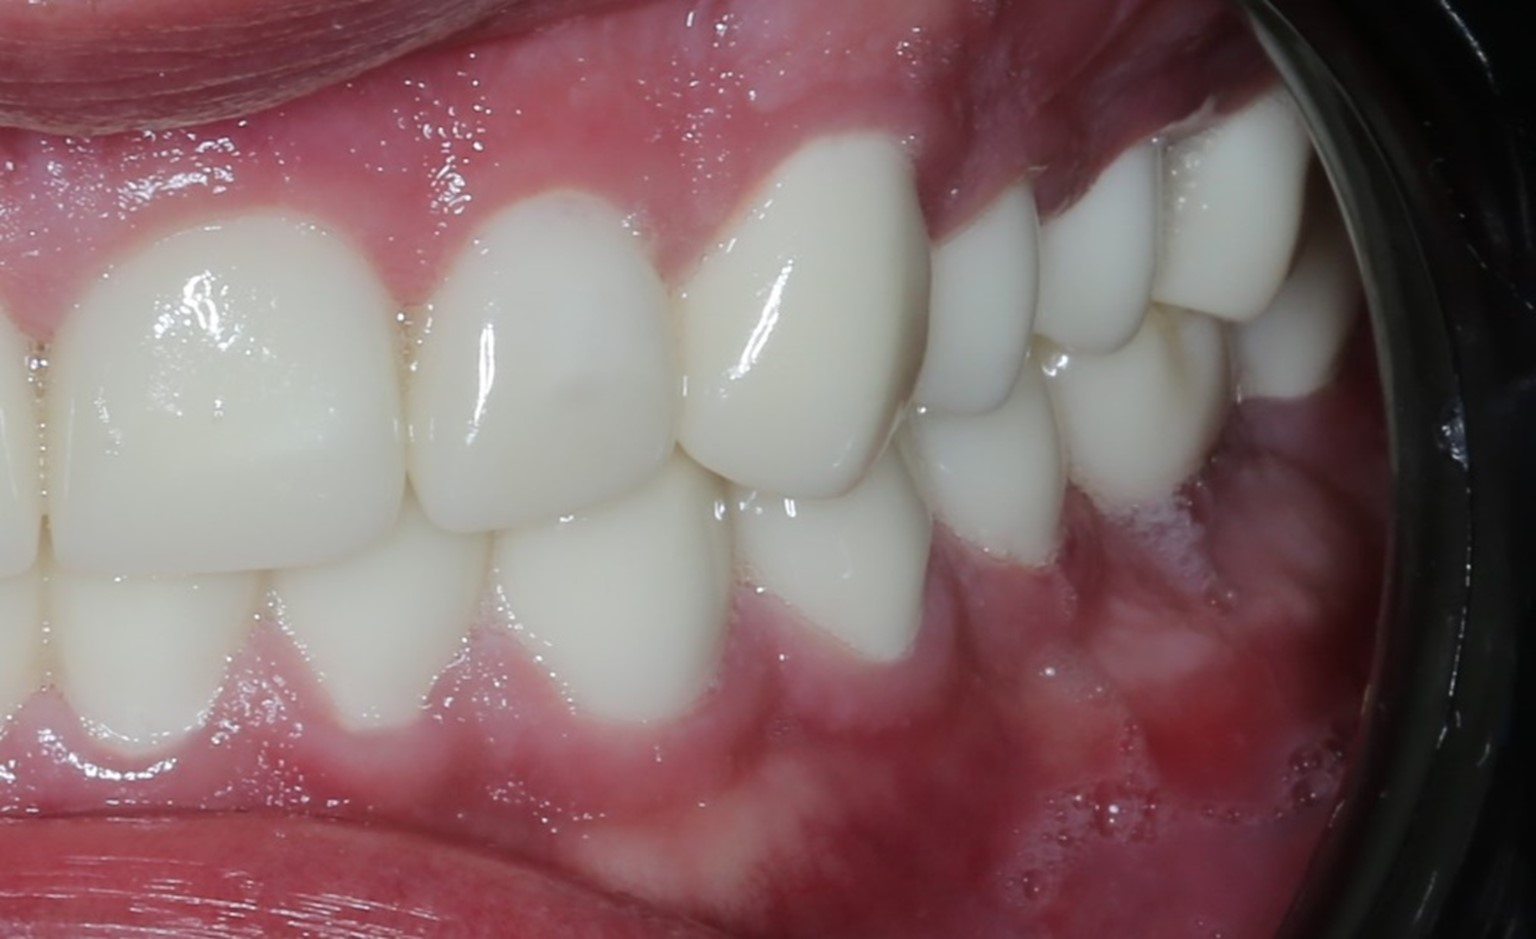

Дальше мы перешли на этап изготовления временных коронок для верхней и нижней челюстей, чтобы прикрыть отсутствующие зубы, куда хирург установил импланты. Где-то они были одиночными, а где-то — мостиком в зависимости от высоты и степени поражения. Они у нас были ровно такими же, как должны были быть и постоянные:

После этого мы обрабатывали зубы, ставили временные коронки под седацией, и сделали несколько несложных коррекций во время ношения временных коронок. Это был достаточно комфортный этап.

На этой фотографии с временными коронками хорошо видно, какого состояния мы добиваемся на момент перепротезирования. Здоровая десна выглядит именно так. Она умеренно увлажнена, розового цвета, не имеет очагов воспаления. Это как раз результат работы с пародонтологом. Он тонкими кюретами прочищает поддесневые зубные отложения, если они есть, и учит пациента правильным гигиене и уходу.